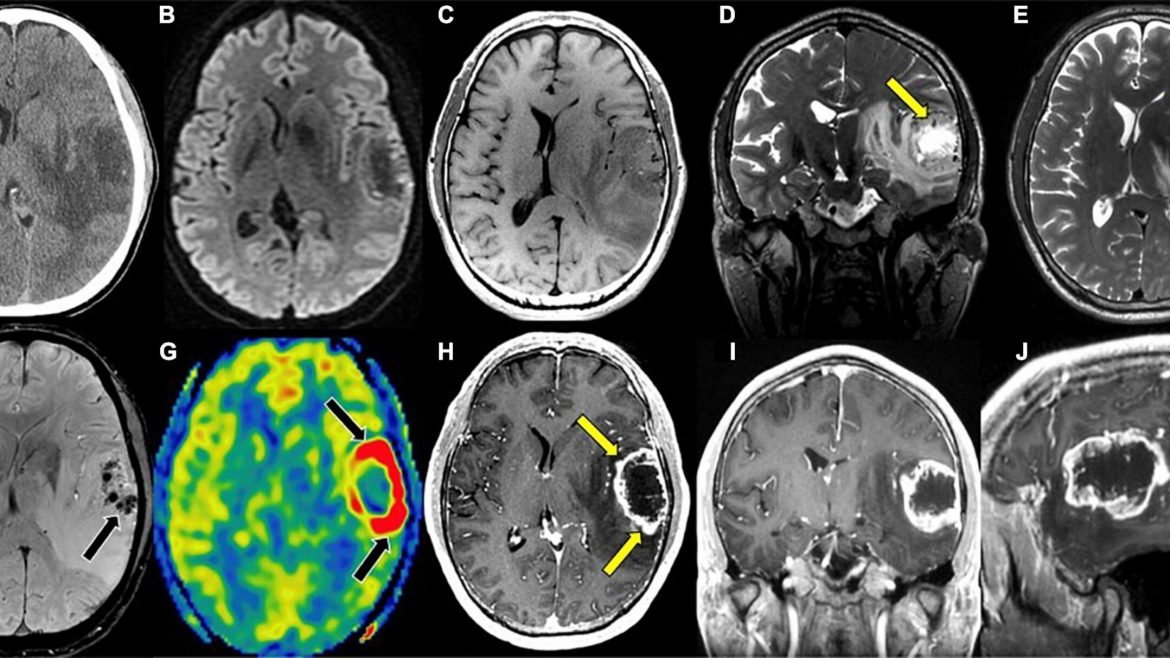

Dr. Scott Adams examined how AI-assisted imaging is redefining medical imaging and expanding access to advanced diagnostics in underserved communities. He also showcased current projects demonstrating how AI can support a more connected, equitable, and sustainable health system.